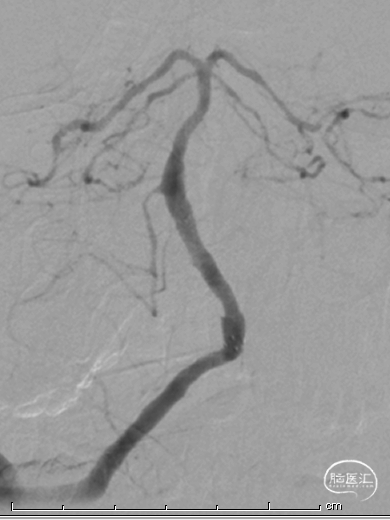

沿微导丝送入XT-27微导管至基底动脉远端,退出微导丝,送入Neuroform EZ 4.0mm×20mm颅内支架,准确定位后释放于狭窄处。观察支架位置良好,残余狭窄轻。

最后影像:椎基底动脉连接处残余狭窄约20%,前向血流改善明显,mTICI3级。远端各血管显影良好,分支较术前增多。